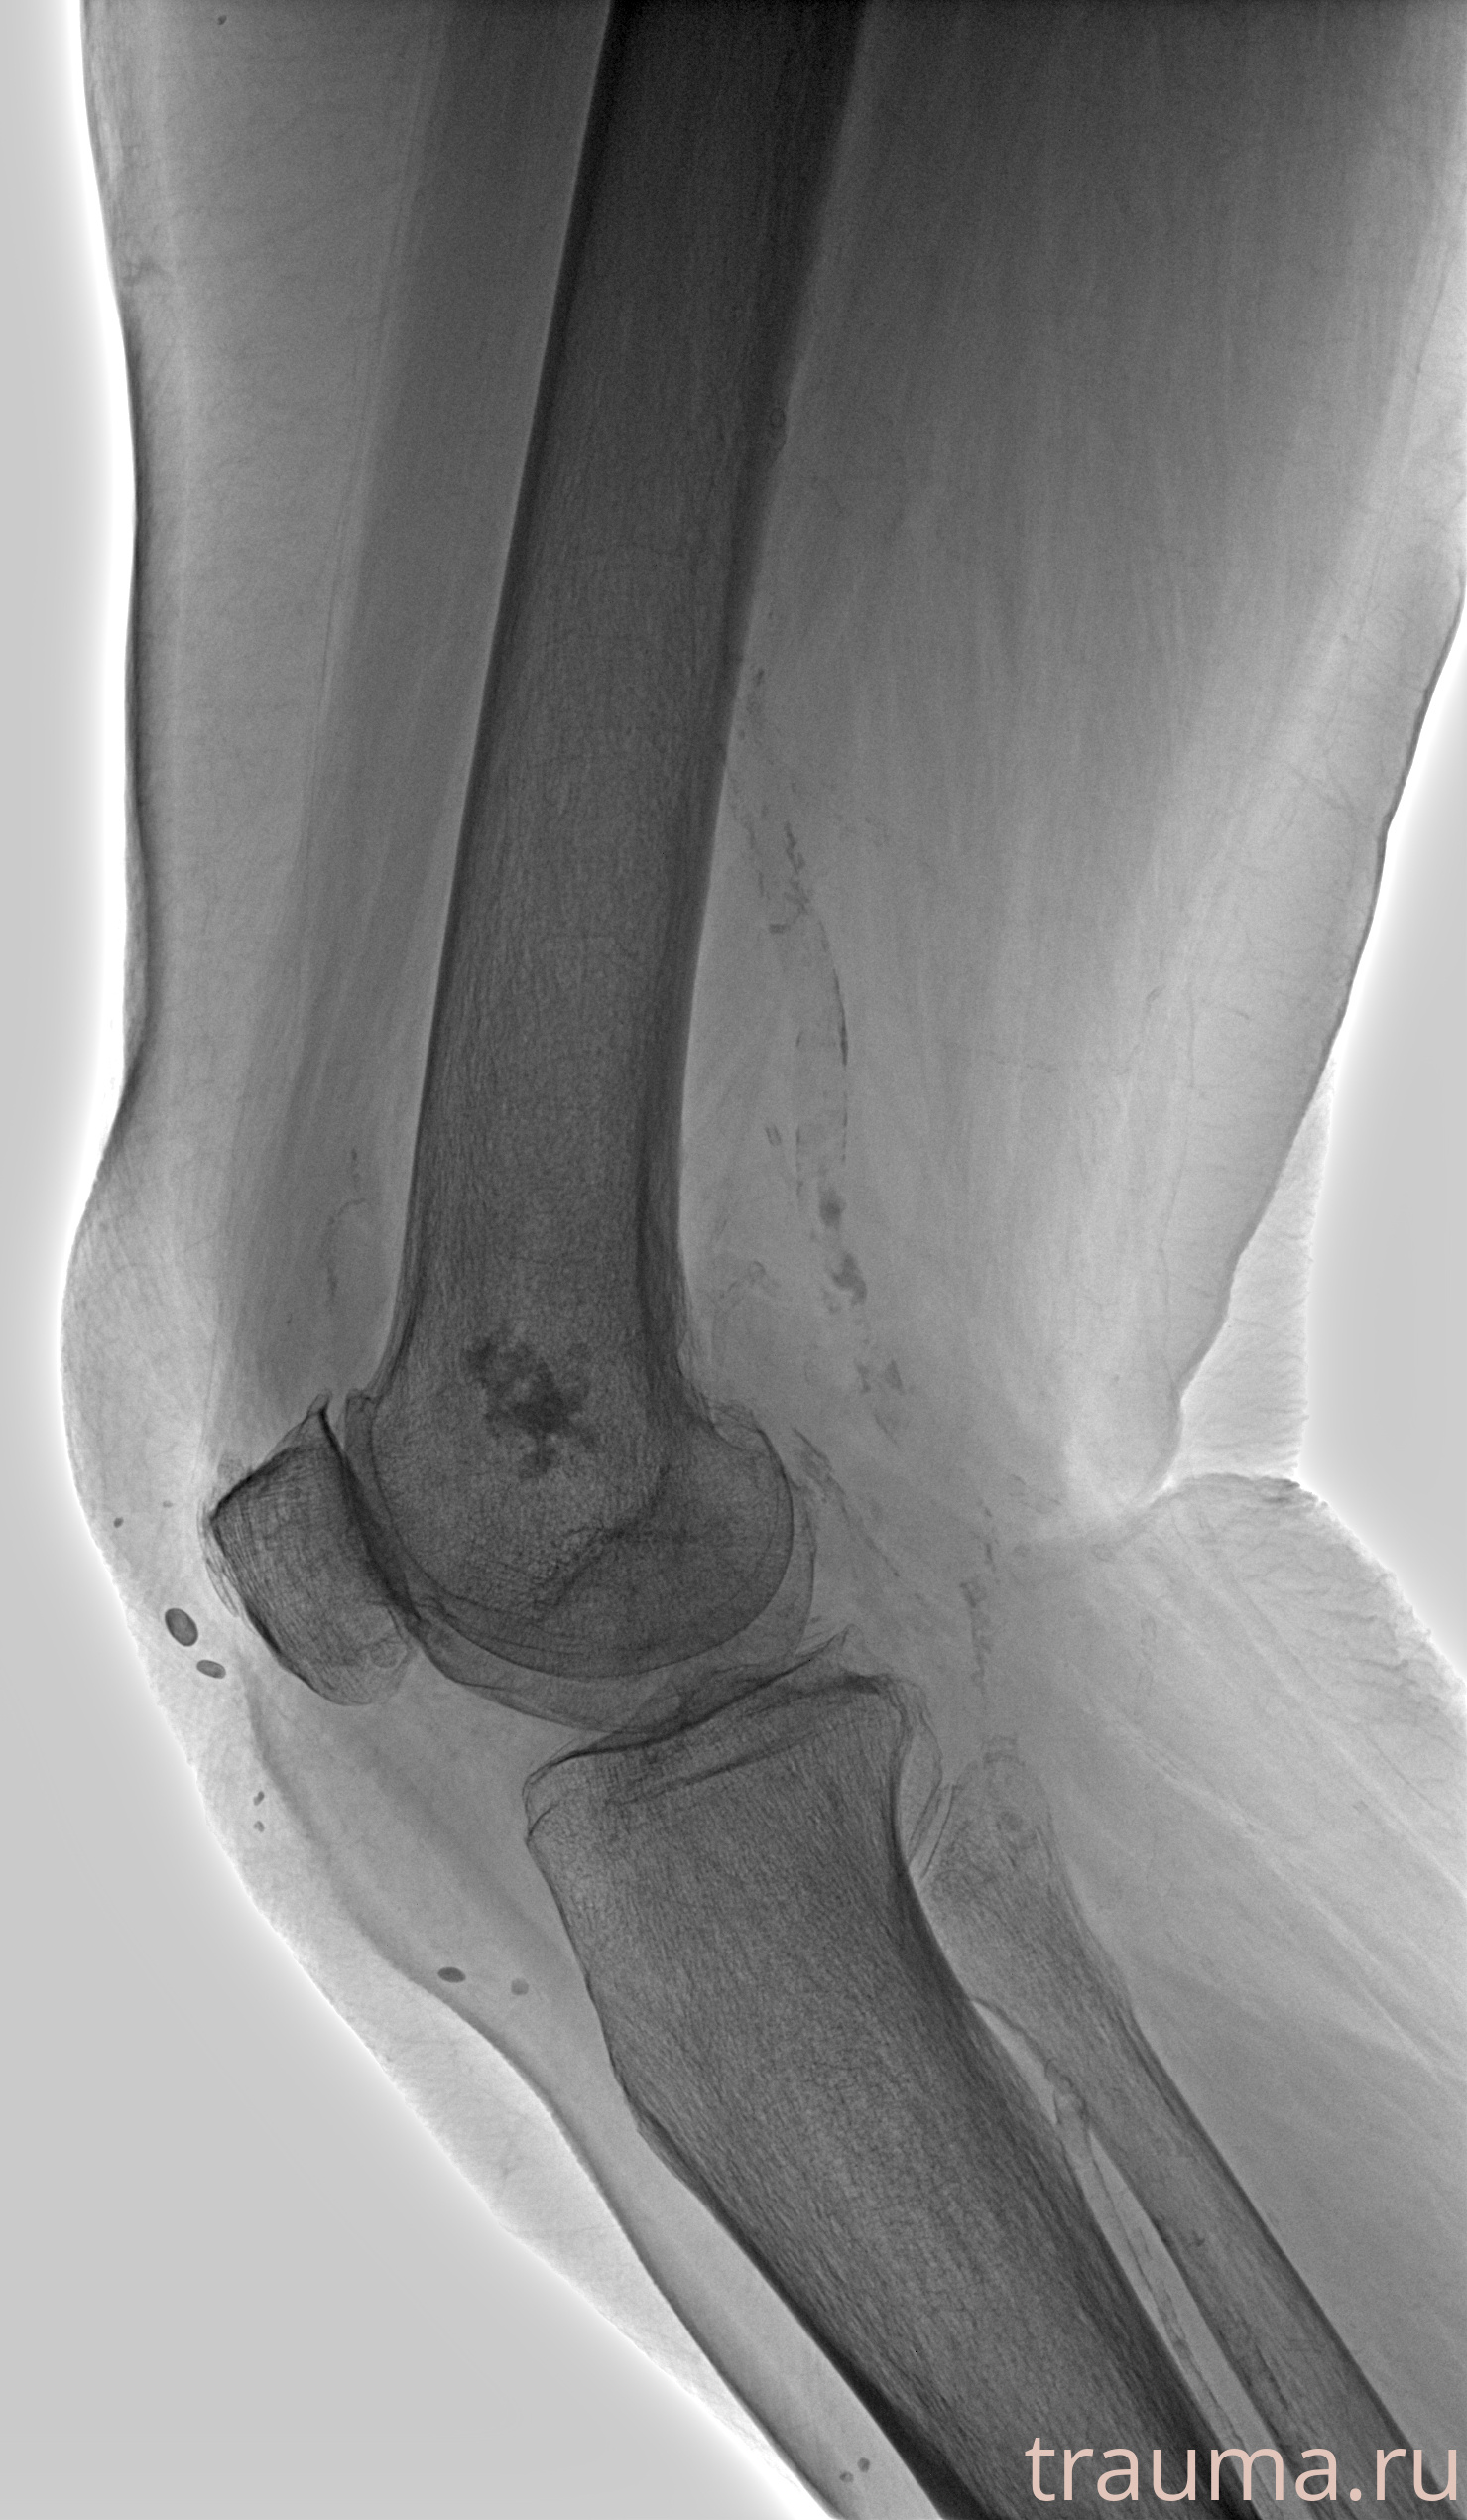

Рентген на дому: по вашему адресу приезжает врач-рентгенолог, травматолог-ортопед с мобильным рентгеновским аппаратом, проводит диагностику травмы или заболевания, делает необходимые рентгенограммы, дает рекомендации по дальнейшему лечению. Получить качественные снимки в домашних условиях возможно благодаря уникальной методике, разработанной МосРентген Центром для института  Склифосовского